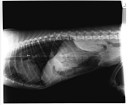

CE estomac chat réponse

Corps étranger 1 – Réponse

22 avril 2012